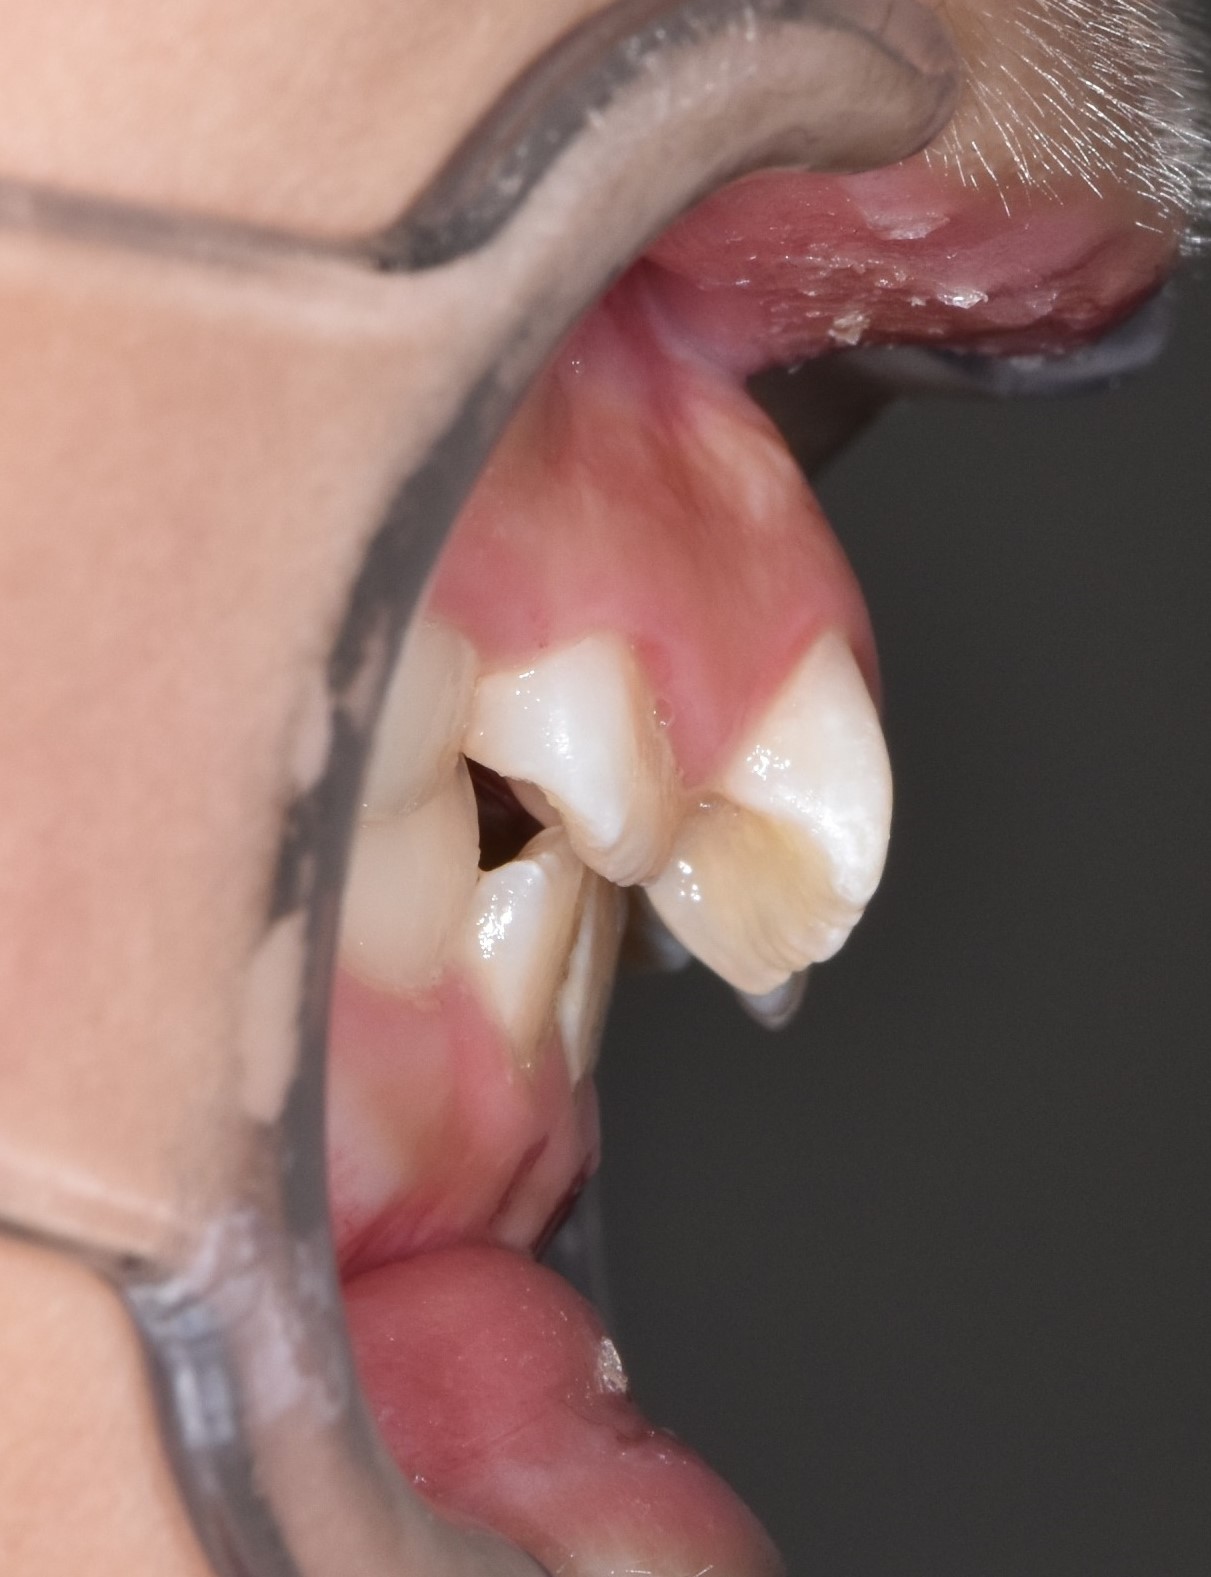

오늘 소개 드릴 케이스는, 서울효앤주니어치과에서 충치치료도 다 하고 정기검진 중, 앞니가 삐뚤게 나고 있어 교정을 하게된 아이입니다.

초진입니다. 위아래 앞나의 공간부족으로 이가 삐뚤뺴뚤 나고있고, 앞니도 뻐드려져있네요.